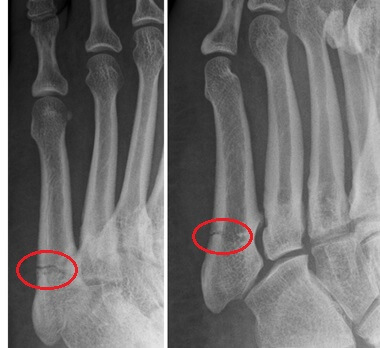

A Jones fracture is a break located in the fifth metatarsal – the long bone that connects the pinky toe to the midfoot. It occurs in a specific area of the bone, between the middle and the proximal end of the fifth metatarsal (close to the midfoot), and is named after Sir Robert Jones, who first described this injury in 1902.

Jones Fractures occur in zone 2, a specific area of the bone which has a particularly poor blood supply, known as a vascular watershed. This limited circulation means Jones fractures can be notoriously slow to heal and are often associated with problems such as non-union (30-50% of cases) and re-fracture (33% of cases).

Distinguishing a Jones fracture from other types of fifth metatarsal fractures is critical because treatment approaches differ significantly due to the poor blood supply. Jones fractures are regarded as the most serious type of fifth metatarsal fracture due to the high risk of delayed union or non-union.